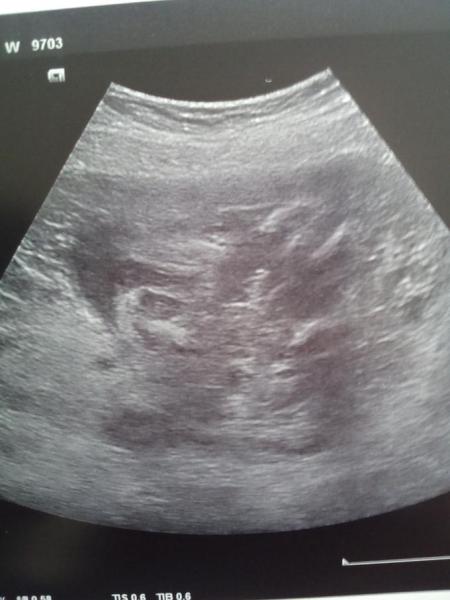

Hallo! Komme gerade vom Ultraschall und was soll ich sagen: Nachdem ich alles auf ein Mädchen verwettet hätte, will mein Arzt das Gegenteil gesehen haben. Scheint so, also würden auch wir zum riesigen Jungsteam zählen. Natürlich freue ich mich auch über einen Jungen (die haben ihre Mamis ja sowieso meist lieber als die Mädels), aber ich bin irgendwie total schockiert, dass mich mein Gefühl so doll getäuscht haben soll... Zumal ich auf dem "Beweisfoto", wie mein Arzt es genannt hat, nichts erkenne Hauptsache die Werte waren alle gut, nächsten Freitag sind wir dann ja zum hochauflösenden US beim Feindiagnostiker. Da sehen wir es dann hoffentlich mit eigenen Augen, bis dahin bin ich noch skeptisch

Bild zu Mutterinstinkt mangelhaft... - Forum für August - Mamis

Also ich musste mich erst mal kurz orientieren wo der Oberschenkel Knochen ist aber ehrlich gesagt sehe ich da schamlippen und nirgends einen Penis.... ich bin gespannt was bei der feindiagnostik raus kommt :-D